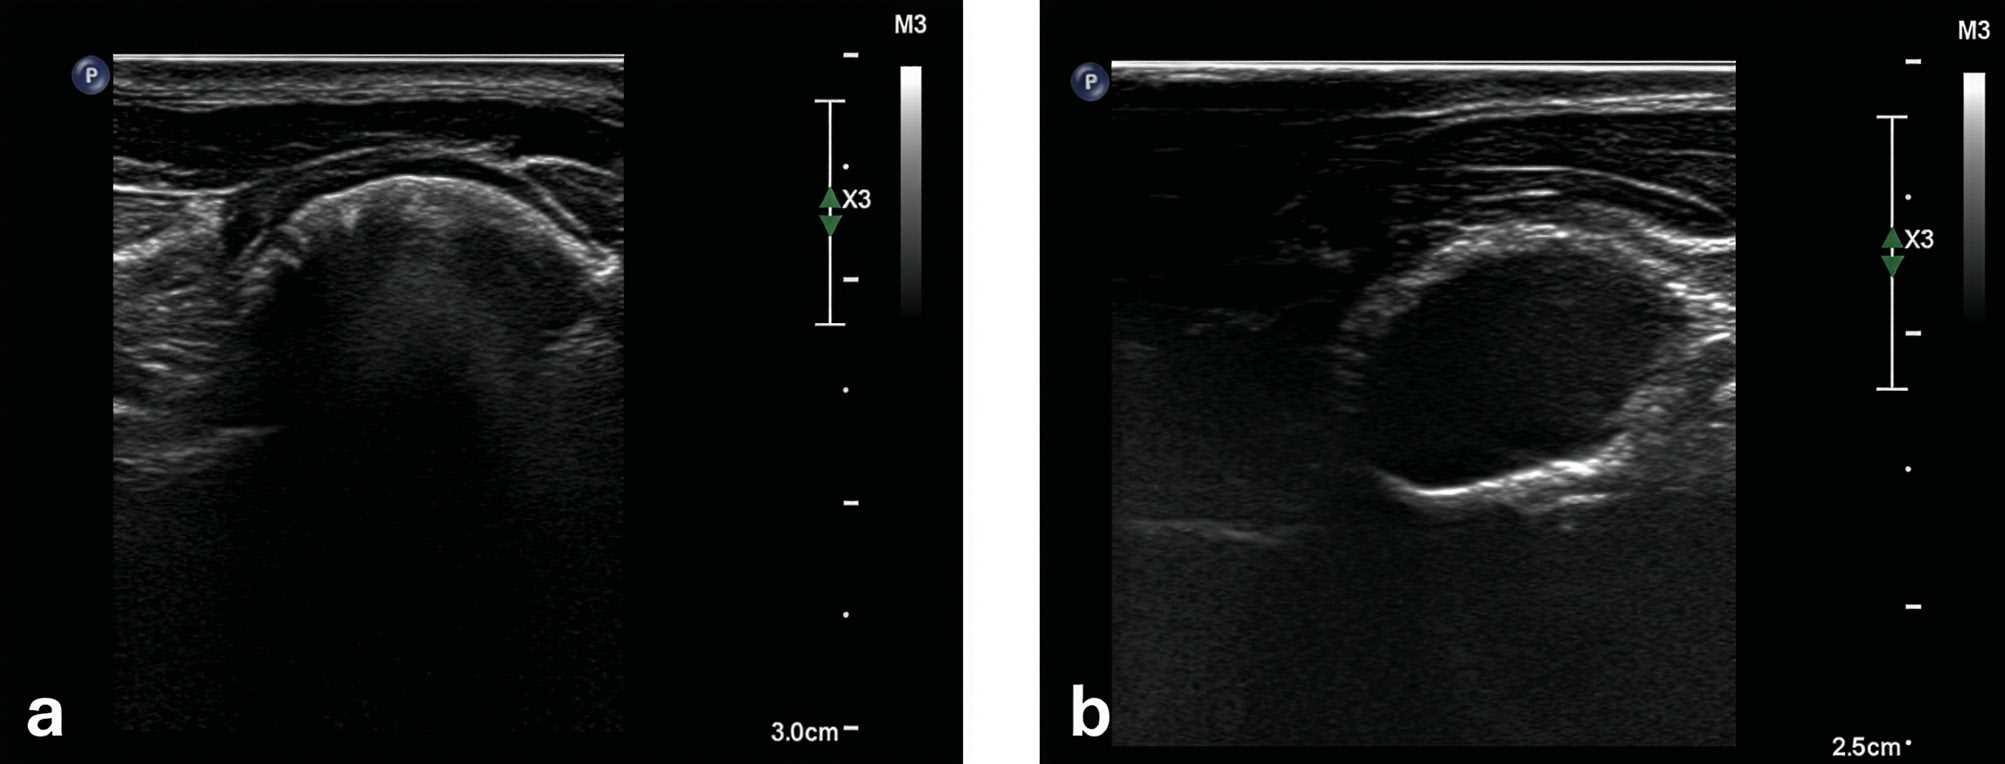

Recientemente se ha documentado la utilidad de la ecografía de las bullas timpánicas en el diagnóstico de la otitis media en los gatos. El menor grosor de la pared de la bulla permite la exploración de la bulla timpánica felina mediante una sonda ecográfica para la detección de contenido líquido en su compartimento ventromedial. Es una opción rápida, poco invasiva y sensible en los pacientes felinos (imagen 10).